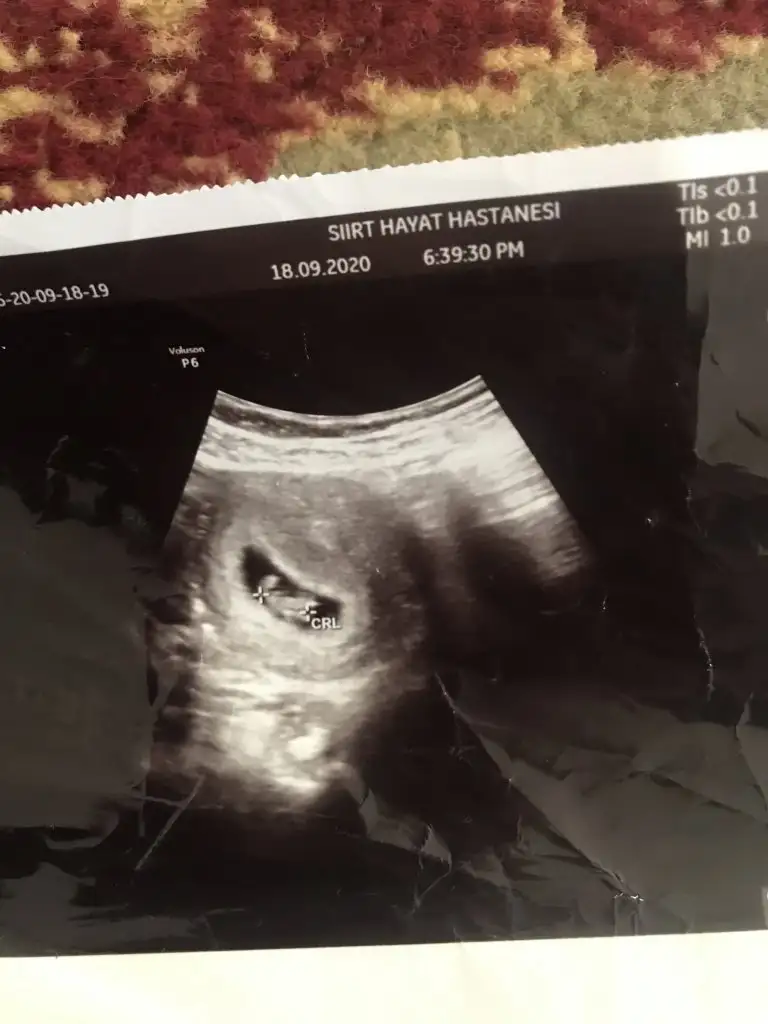

Merhaba İkra meyra canım yine rahatsız ediyorum 13 haftalık ultrason cinsiyet tahmini nedir acaba:)) ?Kız gibi ama en iyi 11 12 13 haftalar olmalı

Onu nasıl anlıyorsunuz ben anlamıyorum ya5 haftalıkken kesenin sağında. Bebeğim kız.yani bende doğru çıkmış.

Sizin ultrasyon resminizde bişey gözükmüyor ki benimkinde net gözüküyor. Sizinki gibi olsa bende anlamazdım.Onu nasıl anlıyorsunuz ben anlamıyorum ya